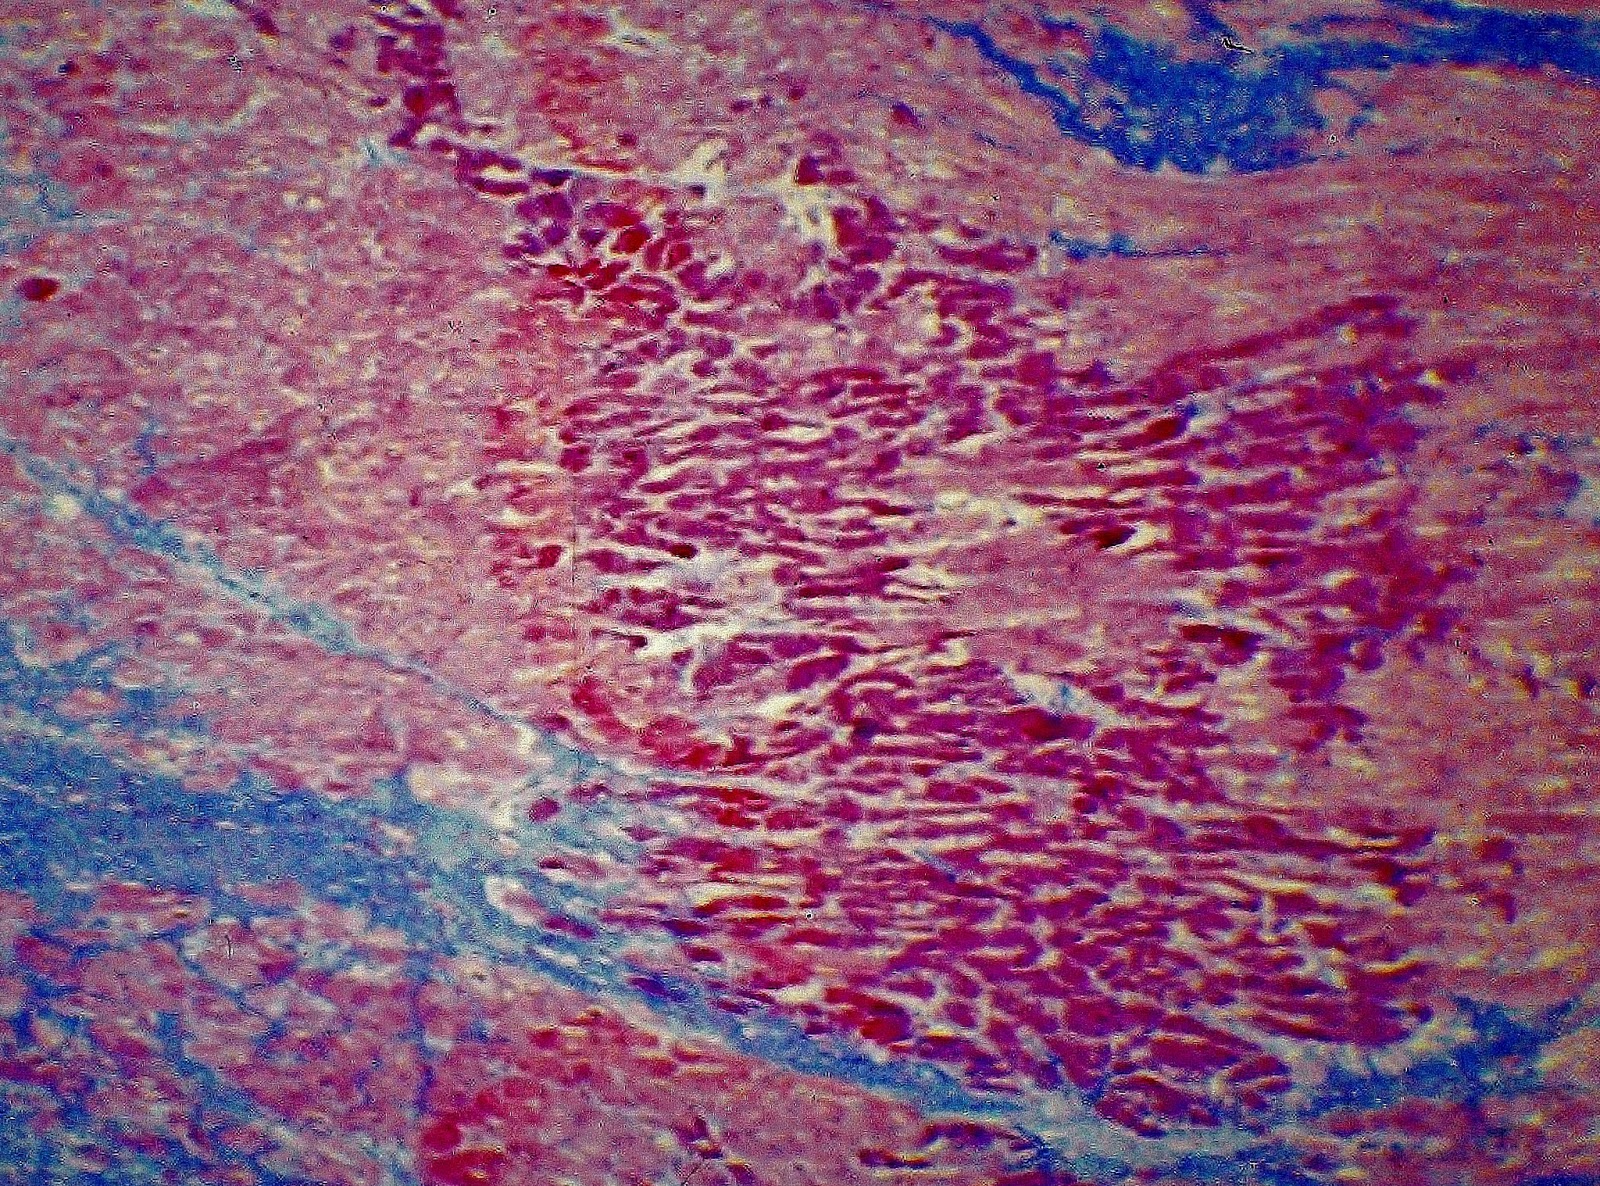

Histopatología

El estudio histopatológico confirmó dicho infarto y demostró la existencia de signos de isquemia micárdica aguda y de una miocardioesclerosis severa.

Blog 135. Caso 3. Fig. 5.-

Blog 135. Caso 3. Fig. 6.-

Blog 135. Caso 3. Fig. 7.-